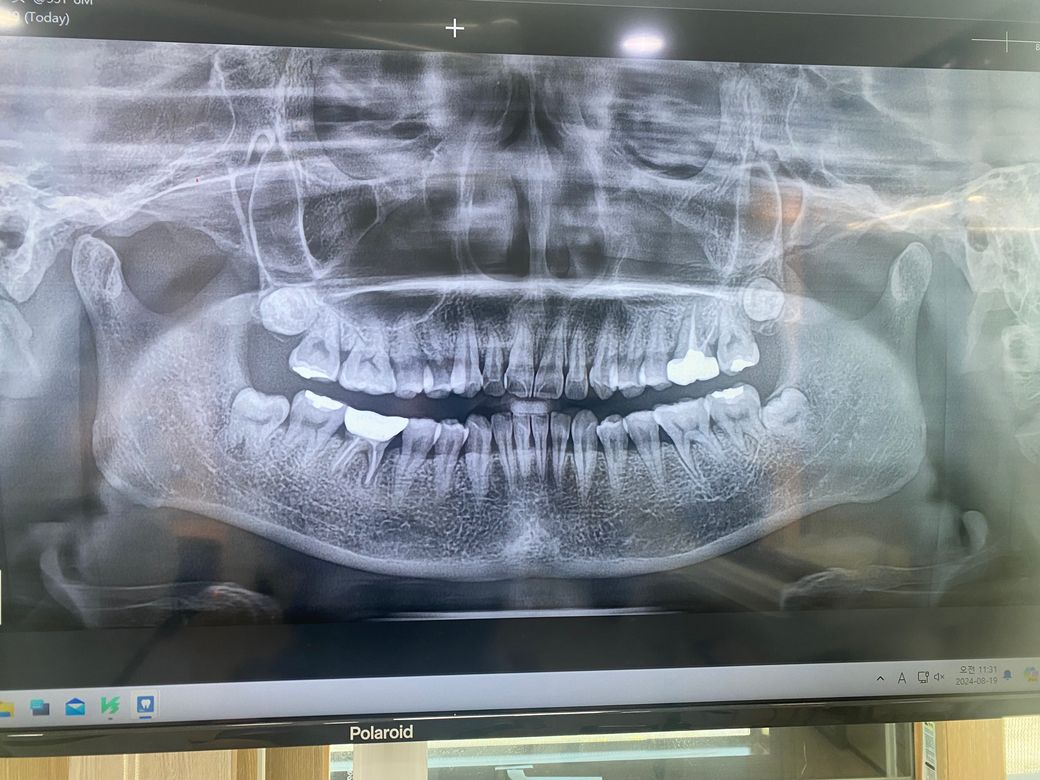

사랑니를 발치할 예정인데 이 부분에 충치여부 좀 알려주세요..

전부 다 잇몸으로 매복된 사랑니이고요

한달 전 엄청나게 붓고 여전히 잘 부어요

매복된 사랑니와 앞어금니 경계의 잇몸이 벌어져있어요

음식물이 껴서 빼려 하는데 혹시 앞어금니에 충치가 있는가요? 사랑니와 인접면 부분이요...

뭔가 거멓게 보이는 저게 뭔지 모르겠어요..

그리고 사랑니가 신경이 닿아있나여? ㅜㅜ

어렵게 빼는지 아닌지도 알려주세요...

-전체 엑스레이

엑스레이 상으로는 사랑니 앞니들의 충치는 없어 보이긴하지만 사랑니 발치를 하고 나서 다시 작은 사진을 찍어보시는게 좋을것같습니다.

앞 어금니 충치 여부는 사랑니 발치 후 다시 한번 사진을 찍어봐야 알 수 있으며 사랑니 빼는 것은 크게 어렵진 않아보입니다.

매복되어 있으며 부분적으로 치조골이 덮고 있기때문에 쉬운 발치는 아닌것으로 보입니다.

사랑니 앞의 치아에는 방사선상에는 음영이 보이지만 실제로는 충치가 있지 않을 가능성이 높습니다.